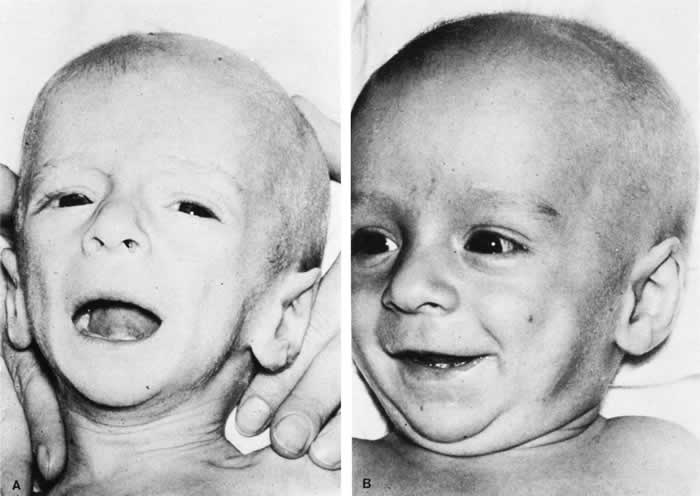

The triad of the SBS includes brain injury usually with hemorrhage, ocular injury, and skeletal injury. These children often have no external signs of trauma. The infant and young child are particularly vulnerable because of their relatively large head, weak cervical musculature, large size of the cranial vault in relation to the size of the brain,3 and immature, unmyelinated brain. Violent shaking causes repetitive anteroposterior and side-to-side disorganized head movement with abrupt acceleration-deceleration forces.7,17,18,19 The magnitude of acceleration-deceleration forces needed to cause brain and eye injuries in humans is extreme but not exactly quantified.20 Although in Caffey's original description, he inferred that normal play activities could cause SBS-like injuries, we now recognize that this is not the case.21

Abusive head trauma is the most common type of child abuse resulting in death,22 although it represents only 3% to 5% of all cases referred to child abuse teams.23 Assault represents more than half of all traumatic brain injury in the first year of life and 90% of brain injuries between 1and 4 years of life. The average age of SBS victim is between 5 and 10 months,22–31 with most children younger than 2 years of age.22,25,26,30 Victims up to 5 years old are rare. The mortality rate of SBS, based on studies with more than 10 patients, is approximately 8% to 61%,23 although this may be a reflection, in part, of separation or imprisonment of perpetrators after the first incident. Recidivism rates are high.

The long-term prognosis for children with brain injury secondary to SBS is poor. In one study, only 28% of survivors had normal neurologic exams on discharge from the hospital; this figure decreased to 8% to 14% in long-term studies.22 Late findings seen on imaging studies include cerebral atrophy, hydrocephalus ex vacuo, chronic subdural effusion, and encephalomalacia. Patients may have quadriplegia, diplegia, hemiplegia, mental retardation, developmental delay; learning disability, seizures (7% to 65%), and psychiatric/behavioral issues(28% to 50%).23,24,26,30,44